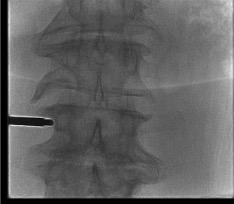

AP View โ "Owl Eye" Pedicle Targeting

- Both pedicles appear as oval or circular targets ("owl eyes") in AP view when the endplate is squared with the fluoroscopy beam

- Advance trocar coaxially within the ipsilateral pedicle oval โ tip should remain inside the pedicle circle throughout advancement

- Trocar medial wall breach (tip crosses the medial pedicle cortex) โ risk of epidural hematoma; stop and recheck

- Final curved cannula tip: at or crossing midline on AP = correct BVF position

- Tip lateral to midline on AP = has not reached BVF; curved cannula entry point too lateral